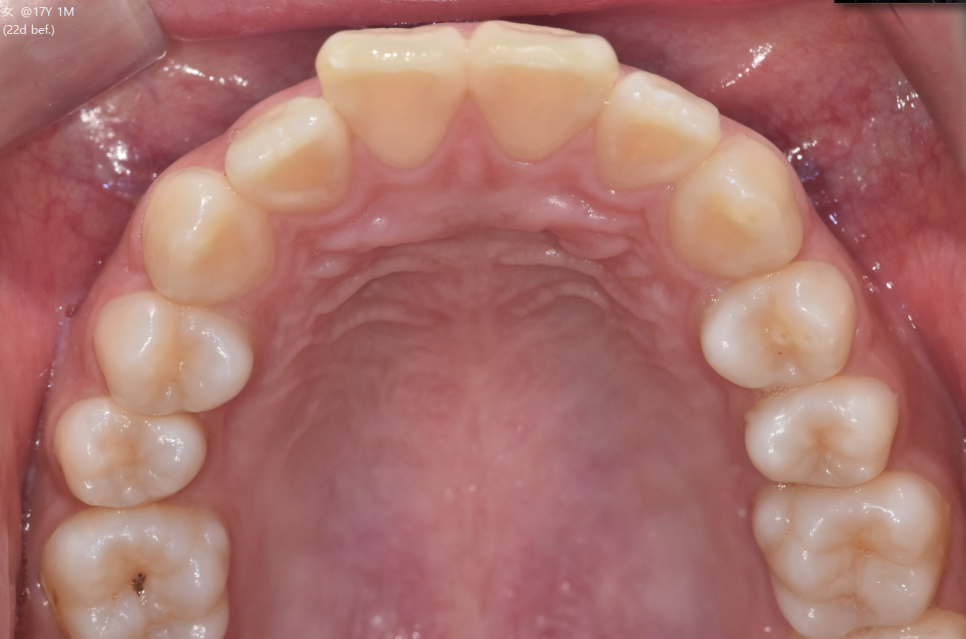

교합 상태, 치아 배열 상태를 확인하기 위해

5분할 포토라 불리는 구강 내 사진을 찍고

뽄도 뜹니다.

교정 모델을 만들기도 하며

이 과정에서 구강 스캐너가 동원되기도 합니다.

앞으로 교정을 통해 치아가 어떻게 움직일지 예측합니다.